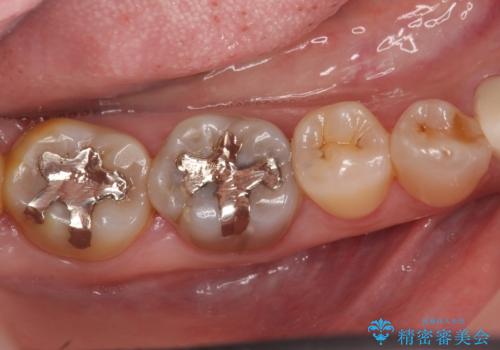

下顎は左側 4 番目から右側 4 番目までの 8 歯と左下 567 ブリッジをオールセラミッククラウンで補綴し、右下67の銀歯はセラミックインレーによる修復を行いました。

セラミックインレーについて

当院のセラミックインレーはemaxという強度と審美性に優れた材料を使用しています。

またプレス方式でインレーを製作しているため、削り出しで製作するCADCAMより優れた適合性も持ち合わせており、虫歯が再発しにくい修復物です。